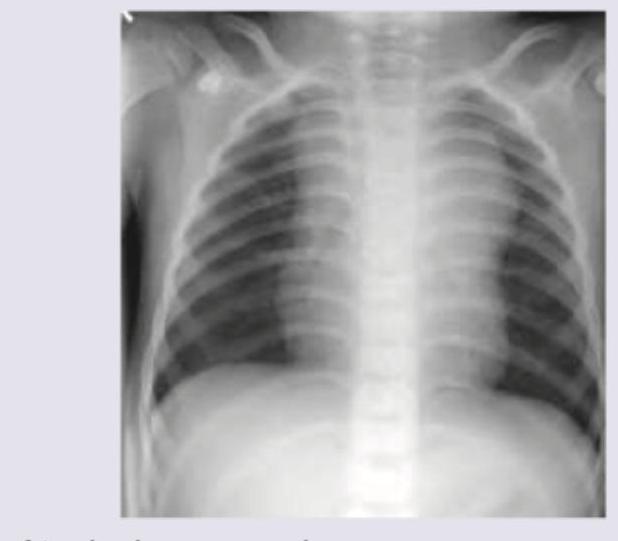

A 2-year-old boy presents with cough and breathlessness for last one month. On examination pallor is present and enlarged liver is palpable 3 cm below costal margin. CXR shows?

Explanation: ***Mediastinal lymphadenopathy*** - The CXR shows evidence of **significant widening of the mediastinum**, particularly in the hilar and paratracheal regions, consistent with enlarged lymph nodes. - In a 2-year-old with chronic cough, breathlessness, pallor, and hepatomegaly, a likely underlying cause could be a condition leading to extensive lymphadenopathy, such as **tuberculosis** or **lymphoma**, which can present with these findings. *Atypical pneumonia* - Atypical pneumonia typically presents with **interstitial infiltrates**, not prominent mediastinal widening. - While it can cause cough and breathlessness, it does not usually explain the **pallor** or **hepatomegaly** observed in this patient. *Pneumonia* - Typical bacterial pneumonia usually manifests as **lobar or segmental consolidation** on CXR, which is not seen here. - Although it causes cough and breathlessness, **hepatomegaly** and **pallor** are not primary features of uncomplicated pneumonia. *Mediastinal fibrosis* - Mediastinal fibrosis is a rare condition that involves diffuse scarring of the mediastinal contents, leading to **narrowing of airways or blood vessels**. - It would typically appear as a more **dense, irregular mass** or diffuse haziness with potential calcifications, often resulting in symptoms related to compression, rather than discrete, enlarged lymph node structures.